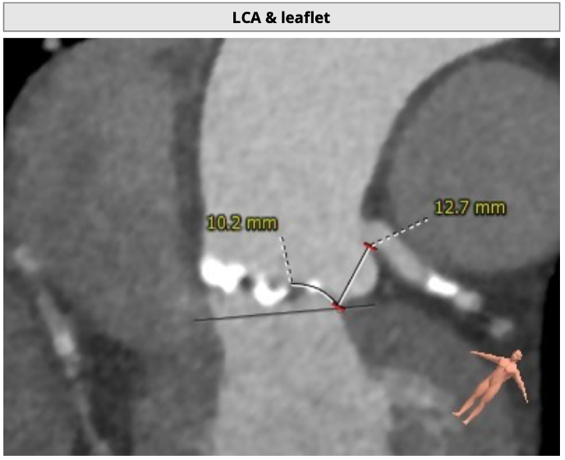

主动脉根部评估

瓣环水平夹角46度